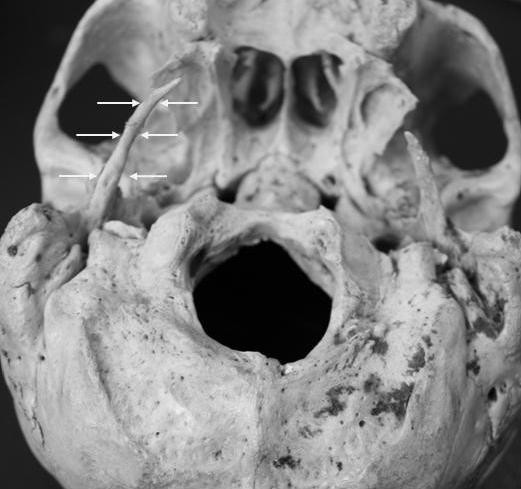

In a dry skull of a male donor cadaver of Caucasian race, aged 72 years old, selected from the osteological collection of our Anatomy Department. From macroscopic analysis an extremely elongated right styloid process was noticed. The measurements were made with the assistance of a digital sliding caliper. The length of the right styloid process was 5.8 cm using as inceptive point the inferior border of the tympanic bone. The left styloid process was 2.3 cm long. The flexure observed at the limit of middle and inferior distal 1/3 could presumably represent the site of the unification between the apex of the process and the ossified section of the stylohyoid ligament (Figure 1 and Figure 2). From the specimens medical history there was no evidence of spondylosis, ankylosing spondylitis or idiopathic skeletal hyperostosis neither any evidence of traumatic lesions at skull base. From case history the specimen was suffering from undiagnosed ipsilateral otalgia. The research done was approved by Ethical Committee of the Aristotle University of Thessaloniki.

Posterolateral view of the skull base, in which a right elongated styloid process, is shown. The flexure observed at the limit of middle and inferior distal 1/3 (arrows) could presumably represent the site of the unification between the apex of the process and the ossified section of the stylohyoid ligament.